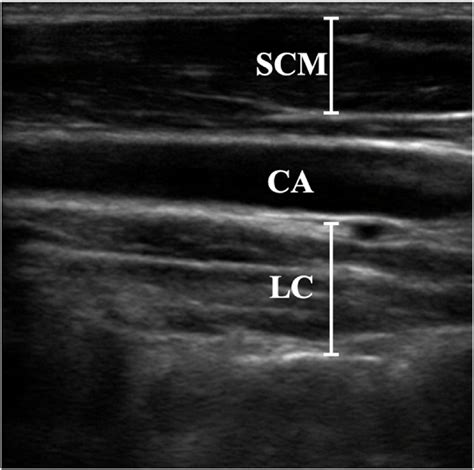

The Longus Colli muscle is a deep cervical flexor, meaning it is situated close to the bone and works to stabilize the neck rather than produce large, powerful movements like the trapezius or sternocleidomastoid. It is anatomically divided into three distinct parts: a superior oblique portion, an inferior oblique portion, and a vertical portion.

Because of its deep location, it acts as a primary stabilizer, acting much like a "corset" for the cervical spine. Its primary roles include: